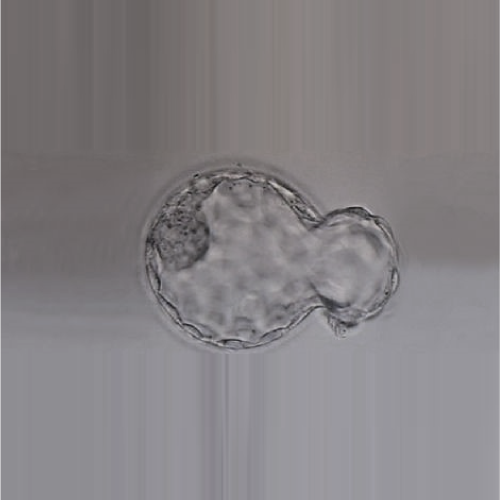

Blastocyst transfer is a strategy in which embryos are cultured to the blastocyst stage before being transferred into the womb during an IVF cycle.

Assisted hatching involves assisting the embryo or the blastocyst to break out of the shell in the IVF laboratory. It is done with the help of a special laser fitted to the microscope.